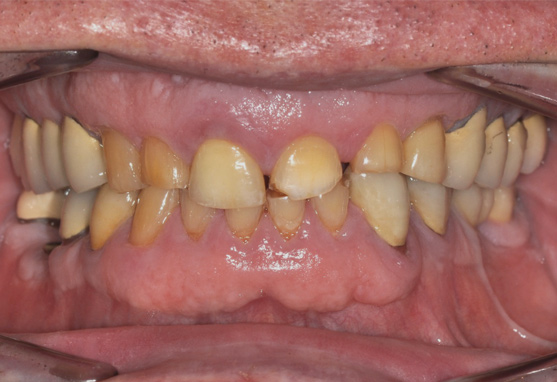

• Minimally invasive preparation. Teeth should be restored using minimally invasive tooth reduction and placement of margins in enamel. Aligning and leveling the cementoenamel junctions of the teeth with orthodontics before restorative preparation minimizes the need for crown reduction and possibly eliminates the need for crown lengthening. In this manner, the treatment no longer has to focus exclusively on the incisal edges. Instead, it can correct the differential extrusion with differential intrusion. For this case, differential intrusion of the anterior teeth was incorporated into removable aligners to level the patient's cementoenamel junctions (Figure 4).

(4.) Postorthodontic anterior bite.

Figure 4